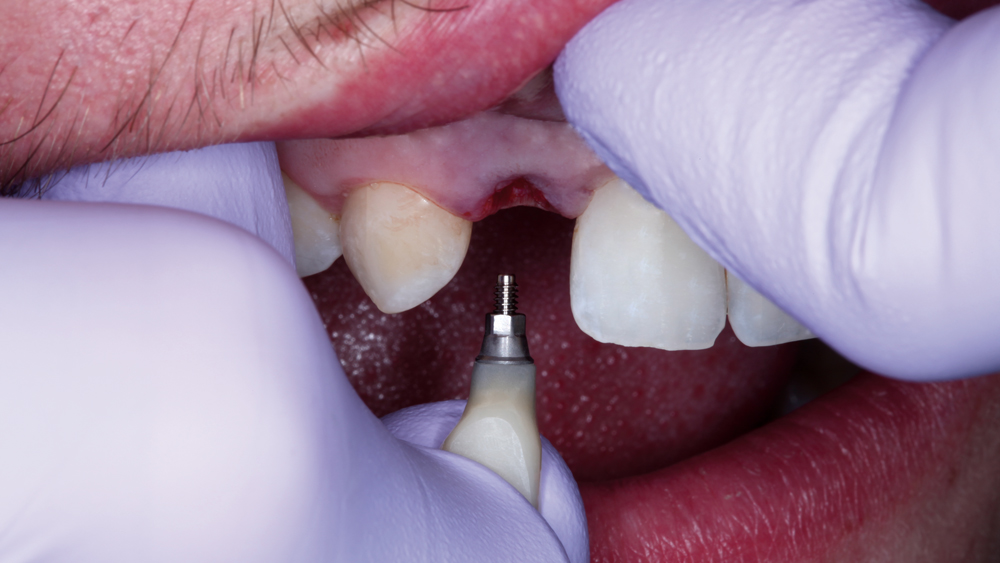

The following case illustrates the efficient, straightforward clinical workflow for placing Hahn Tapered Implants via guided surgery. A digital treatment plan is developed in which a 3.5 mm implant is positioned to support the ideal prosthetic outcome. An immediate provisional crown is designed in concert with the surgical guide and delivered at the time of surgery, helping to produce a predictable, highly esthetic restoration for a demanding case in the smile zone.